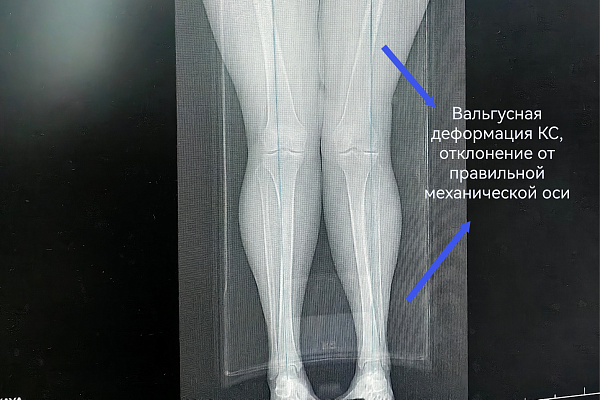

Чтобы избавиться от мучительной боли в колене, наша 55-летняя пациентка готова была избавиться от всего сустава. При госпитализации женщина настроилась на эндопротезирование. Однако травматологи-ортопеды выбрали другую тактику. При вальгусной деформации и деформирующем артрозе второй стадии коленный сустав оставался достаточно сохранным. Чтобы спасти его от замещения металлоконструкцией, была выполнена корригирующая остеотомия.

Суть операции – в исправлении нарушенной оси конечности. После перестроения и выравнивания костей голени нагрузка собственного веса смещается с пораженной части сустава на здоровую. Таким образом, болевой синдром регрессирует, а износ сустава замедляется.

Технически корригирующая остеотомия не представляет сложности. Непосредственно в операционной для опытного хирурга работы - на полчаса. А вот предварительное планирование – это целое исследование с множеством математических измерений и расчетов. В профессиональной среде говорят, что такая операция делается в основном в ординаторской. И это действительно так. До хирургического вмешательства врач должен предельно точно определить ось конечности, градус её отклонения и угол коррекции.

В случае с этой пациенткой ради сохранения коленного сустава пришлось пожертвовать 10 миллиметрами большеберцовой кости. Костный клин такого размера был удалён, чтобы вернуть конечность в правильную механическую ось. Небольшие размеры современных фиксаторов позволяют выполнять операции малотравматичным доступом – через 4-5-сантиметровый разрез.